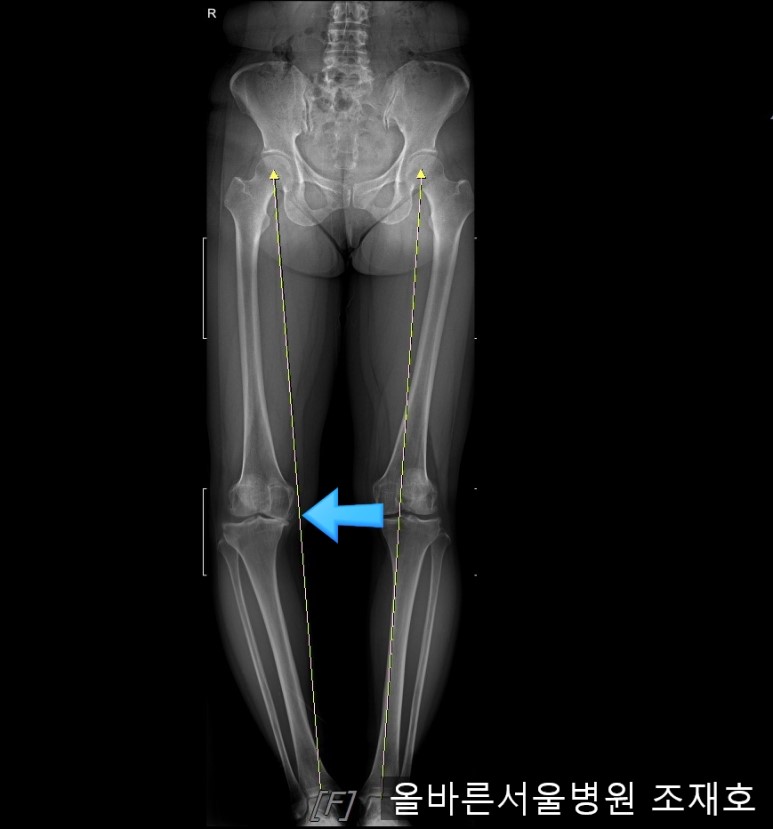

仅通过放射线片子观察到:右膝由于炎症严重,内侧胫骨及股骨已接触在一起,向内测严重变形。

左膝虽然也观察到了炎症,但远不如右膝严重。

观察膝盖下肢排列的扫描图像可看到右腿严重变形,身体中心向内倾斜。